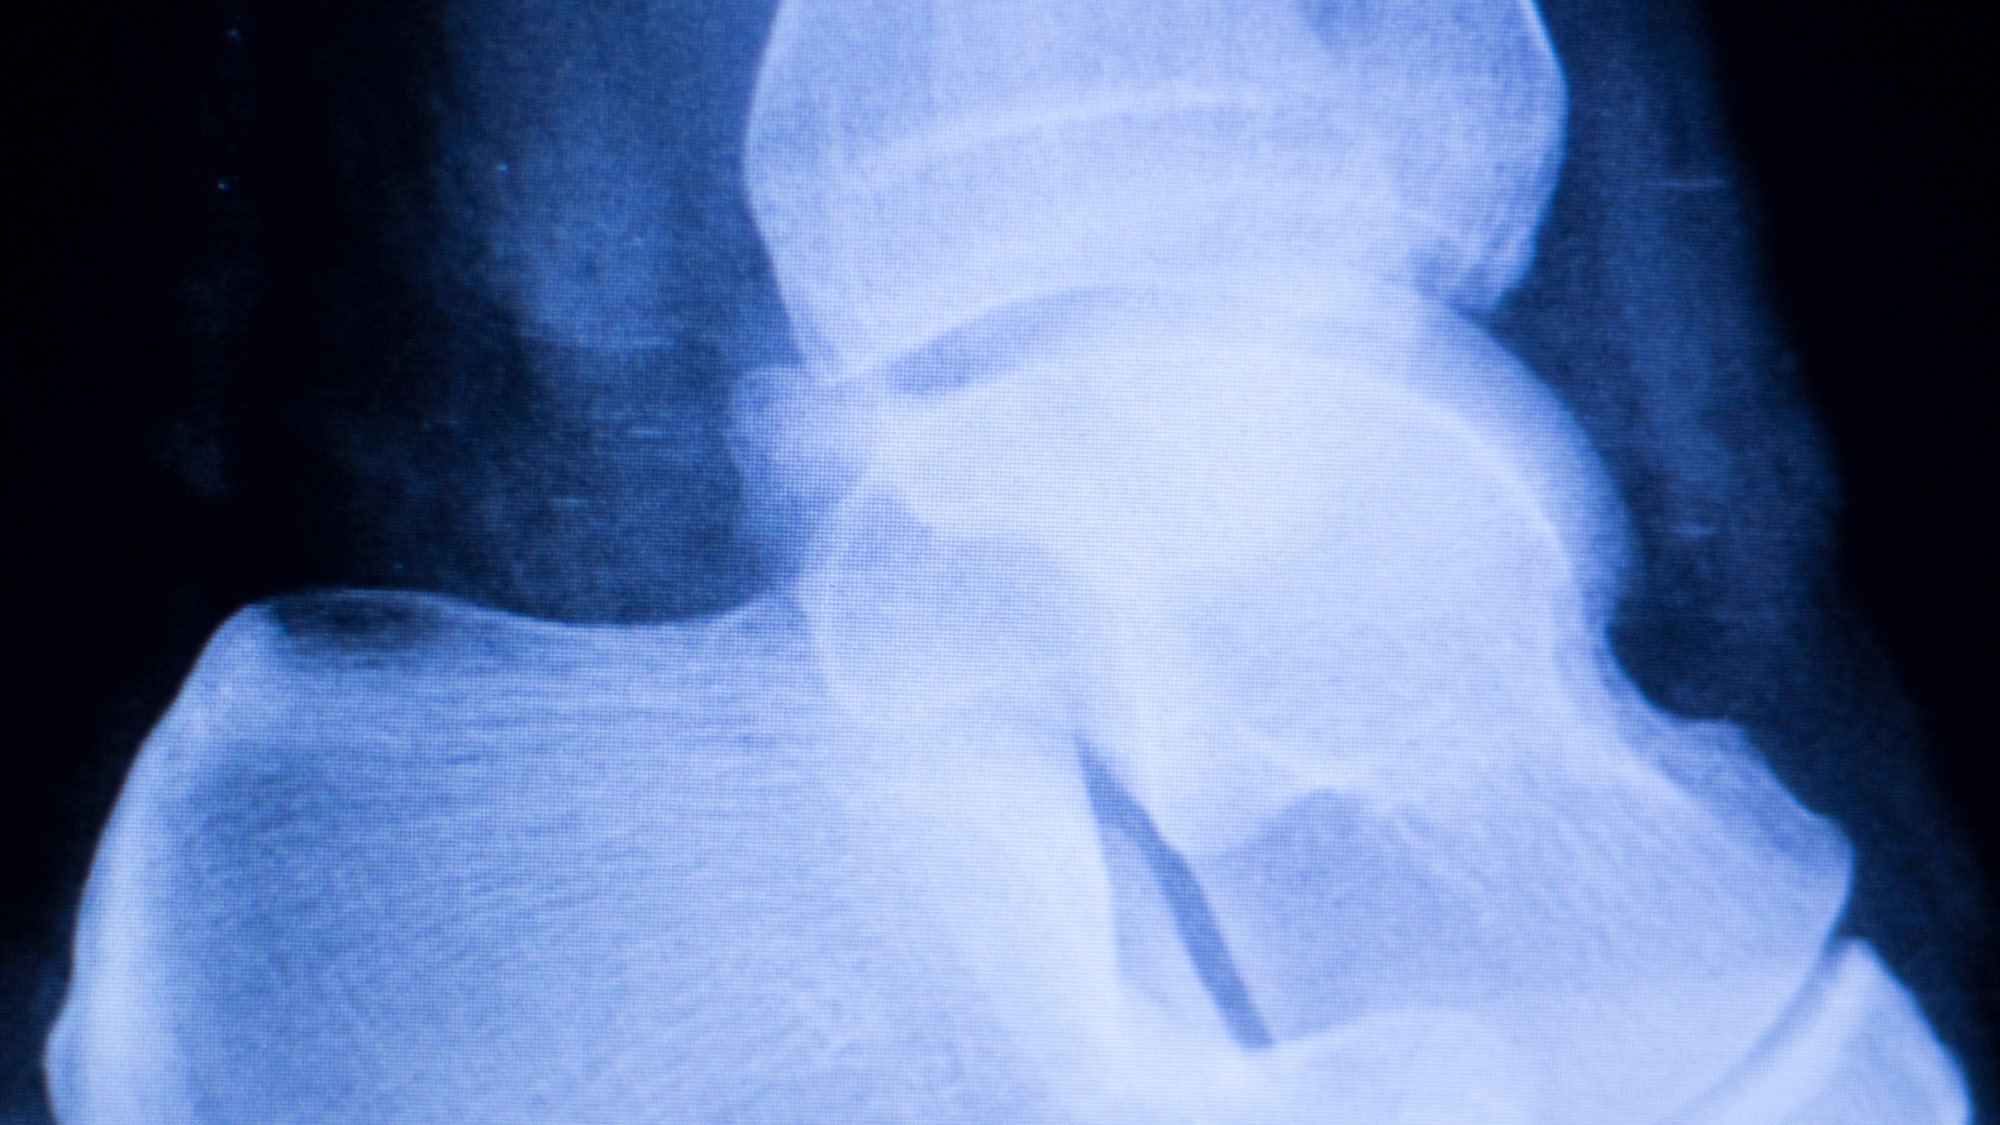

Bone Spurs

The plantar fascia runs along the bottom of your feet from your heel bone to end of your feet. Increasing stress and strain along the plantar fascia results in inflammation and microtears along the origin of the plantar fascia, or where the plantar fascia starts on the heel bone. The inflammation and microtears that occur causes the heel bone to respond with calcifications that extend out along the path of the plantar fascia.

The bone spur is the RESULT of heel pain not the CAUSE of heel pain.